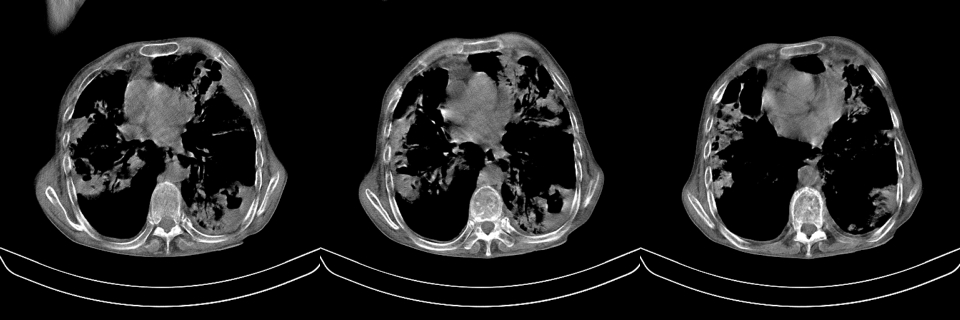

以下是引用mzh123在2007-8-26 19:58:00的发言:[br]两肺弥漫性斑片改变,其中可见大小不等之不规则空洞,结合既往病史还是考虑结核复发及感染。

以下是引用云翔在2007-8-26 20:54:00的发言:[br]这是44岁的肺吗?是否有先天病的基础?干酪性肺炎?